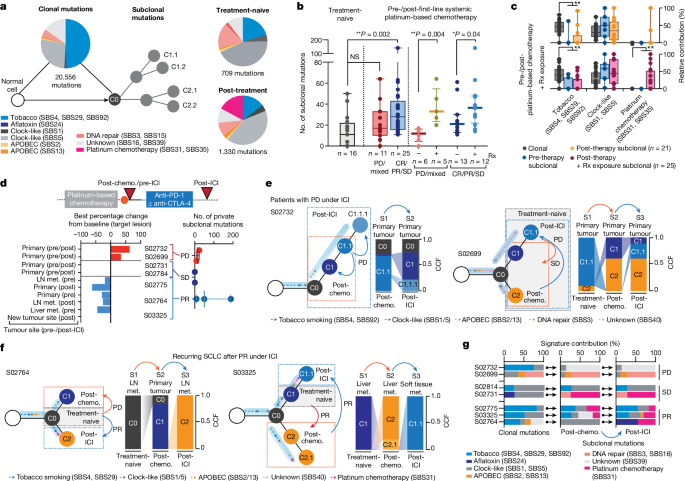

Mutation signatures of clonal diversity

To pinpoint the underlying processes that cause the observed treatment-dependent increase in clonal diversity, we determined signatures for mutations defining the common ancestor and subclones 17 . Confirming previous studies in lung cancer 18 , 19 , 20 , 21 , age-like and tobacco-associated processes dominated within the mutations of the common ancestor, which correlated with the level of smoking in these patients (Spearman correlation = 0.39, ** P < 0.01; Fig. 3a and Extended Data Fig. 2a,b ). Furthermore, clonal mutational processes in some patients were related to apolipoprotein B messenger RNA-editing enzyme, catalytic polypeptide (APOBEC), defective DNA repair and aflatoxin, the latter previously associated with lung cancer 22 . Mutational processes assigned to subclones were less frequently associated with tobacco exposure, and we observed a predominance of clock-like signatures shaping subclonal mutations in both treatment-naive and recurring tumours (Fig. 3a–c and Extended Data Fig. 2c ), implying that branching from ancestral clones involved acquisition of mutations at a steady rate, which may have happened earlier throughout the patient’s lifetime 21 . We furthermore identified, in a subset of patients, mutational patterns associated with platinum-based chemotherapy (single-base substitutions SBS31 and SBS35), which were presumably acquired during first-line chemotherapy 23 , 24 (Fig. 3a and Extended Data Fig. 2d ).

a , Mutational signatures of SBS assigned to clonal (ancestral clone C0) and subclonal mutations in treatment-naive and post-treatment tumours. b , Subclonal mutations determined for multiregional samples from treatment-naive patients (grey, left) and for tumours pre-/post-first-line systemic platinum-based chemotherapy (middle and right). Patients are grouped according to clinical response (middle) and exposure of relapsing tumours to previous radiation. Median and interquartile range, minimum and maximum values. Mann–Whitney U -test, two-sided, * P < 0.05, ** P < 0.01. c , Mutational signatures for paired pre-/post-treatment samples from patients receiving chemotherapy. Relative contributions assigned to clonal (grey) and subclonal mutations of pre-therapy (blue) and post-therapy tumours exposed to platinum-based chemotherapy (blue, n = 21) and to additional site-specific radiation (pink, n = 25). Median and interquartile range and whiskers (minimum and maximum values). Paired two-sided Wilcoxon test, ** P < 0.01. d , Seven patients were receiving second- or third-line treatment with ICI, and the scheme for their clinical course is shown in Fig. 1b . Waterfall plot showing tumour site-specific response to ICI (lower right). Numbers of private subclonal mutations pre- and post-ICI, grouped according to clinical response (lower right, median with maximum and minimum values). e , f , Clonal dynamics at first diagnosis (treatment-naive, grey box), at relapse following first-line chemotherapy (post-chemotherapy, orange arrows and dashed box) and following treatment with ICI (post-ICI, blue arrows and dashed box). Arrows assigned to branches of clone trees indicate the relative contribution of mutational signatures in ancestral clone C0 and subclones. Site-specific CCFs of tumour clones are plotted. Clinical response to the respective treatment is indicated, distinguishing patients with progressive disease ( e ) and partial response ( f ) under ICI. g , Relative contribution of mutational signatures in patients receiving ICI assigned to clonal and subclonal mutations of tumours post-chemotherapy and post-ICI. NS, not significant.

We proposed that the extent of subclonal diversity and associated mutational signatures at relapse relate directly to the type and efficacy of previous treatment. Patients with clinical response to systemic treatment with first-line platinum-based chemotherapy exhibited a significant increase in subclonal mutations when analysing tumours before treatment and at relapse (** P < 0.01); by contrast, the number of subclonal mutations in specimens before and after chemotherapy from patients with refractory SCLC did not differ significantly compared with the level of subclonality determined for multiregional samples in treatment-naive patients (Fig. 3b ). These observations support the notion that treatment fails to suppress the original dominating clone in chemorefractory patients whereas successful chemotherapy eliminates the most abundant clone, which is followed by the observed expansion of a multitude of subclones.

The level of subclonal mutations differed substantially across samples (Fig. 3b ), and we could not identify specific mutational processes that related to the efficacy of chemotherapy in these patients (Extended Data Fig. 2e ). By contrast, independent of the overall clinical response, we found a significant increase in subclonal mutations when analysing those tumour sites at relapse that had also been exposed to radiotherapy (Fig. 3b and Methods ). Ionizing radiation does not typically induce signatures marked by single-base substitutions, and we could not identify other signs of radiation-induced DNA damage in tumours at relapse 25 (Extended Data Fig. 2f ). To our surprise, however, paired studies of pre- and post-therapy tumours frequently showed platinum-associated genomic scars in those sites previously exposed to radiotherapy (Fig. 3c and Extended Data Fig. 2g–i ). The mutational patterns that underlie platinum damage have previously been identified both analytically and experimentally 23 , 24 , and our own confidence in the respective assignments is based on both the large number of specimens (26%, n = 12 of 46) and significant increase in platinum damage in tumours at relapse (** P < 0.01; Fig. 3c , Extended Data Fig. 2d and Supplementary Table 5 ). Although we have no formal explanation for this observation, our data are compatible with the view that marked tumour growth suppression by radiotherapy permits the outgrowth of diverse subclones, including tumour clones that had acquired genomic scars from previous lines of chemotherapy 23 .

Tumour evolution under immunotherapy

We reasoned that the burst in clonal diversity induced by chemotherapy might impact the efficacy of any subsequent treatments such as ICI. We therefore analysed the evolutionary dynamics in seven patients who had received, as second- or third-line treatment, the PD-1 inhibitor nivolumab, alone or in combination with the CTLA-4 inhibitor ipilimumab (clinical trial no. NCT03083691 ). We sampled tumour biopsies before and after treatment with ICI, and in five patients we also performed comparisons with the treatment-naive tumour acquired at the time of first diagnosis (Figs. 1b,c , 2d and 3d and Extended Data Fig. 3a ). Two patients experienced disease stabilization throughout treatment with ICI and, in agreement with radiological disease assessment, subclonal tumour cell populations before and throughout immunotherapy were conserved (Fig. 3d and Extended Data Fig. 3b,c ). Two patients who progressed under immunotherapy exhibited a limited but detectable change in subclonal mutations, and assignment of tumour clones showed shifts to ancestral clones already existing before the initiation of ICI (Fig. 3d,e and Extended Data Fig. 3b ). Thus, tumour progression under immunotherapy led to the expansion of subclones already extant at the time of relapse. This was similarly observed in one patient who experienced an initial clinical response to ICI (S02775; Extended Data Fig. 3d ). By contrast, two patients who experienced tumour shrinkage under ICI showed an increase in subclonal mutations at the time of relapse (S02764 and S03325; Fig. 3d and Extended Data Fig. 3b ). In comparison with corresponding treatment-naive tumours, we found that these subclones originated from ancestral clones that were dominant at the time of first diagnosis in these patients (Fig. 3f ). Thus, tumour clones that initially dominated tumour sites at the time of first diagnosis—and that had effectively been suppressed by first-line chemotherapy and not identified at the time of relapse—reappeared and provided the seed for tumours causing relapse following subsequent lines of immunotherapy. Furthermore, similar to our observation in irradiated tumours, recurring tumour clones dominating at relapse following effective immunotherapy exhibited imprints of platinum-based DNA damage ( n = 4 of five patients with stable disease and partial response; Fig. 3f,g , Extended Data Fig. 2c and Supplementary Table 5 ). The emerging subclone with signs of platinum-based DNA damage was not detectable at the time of relapse from first-line chemotherapy in two patients—before initiation of successful treatment with ICI (Fig. 3g ). Of note, the tumour obtained before immunotherapy from patient S03325 contained a subclone with a signature of platinum-based DNA damage, which was different from that detected at the time of relapse post immunotherapy. Furthermore, patient S02764 was refractory to chemotherapy, with a limited subclonal drift following first-line chemotherapy (Fig. 3g and Supplementary Appendix ). However, in both patients, at relapse from initially effective second-line immunotherapy, ancestral clones emerged with acquired platinum-related DNA damage, presumably acquired throughout ineffective first-line treatment with chemotherapy.

Taken together, our data show that derivatives of earlier ancestral clones persisted, despite the disappearance of the original dominating clone following first-line therapy, and then reappeared under subsequent lines of therapy thus causing clinical relapse. We could not identify any specific mutational processes or genomic patterns that resulted only from treatment with ICI and that might be indicative for effective ICI therapy. However, our data emphasize that, regardless of the efficacy of first-line treatment, ancestral clones appear to acquire platinum-induced DNA damage throughout first-line chemotherapy. Radiation, or other effective second- or third-line line therapies, can permit the subsequent expansion of these clones, even in the evolutionary short time interval of clinical care.